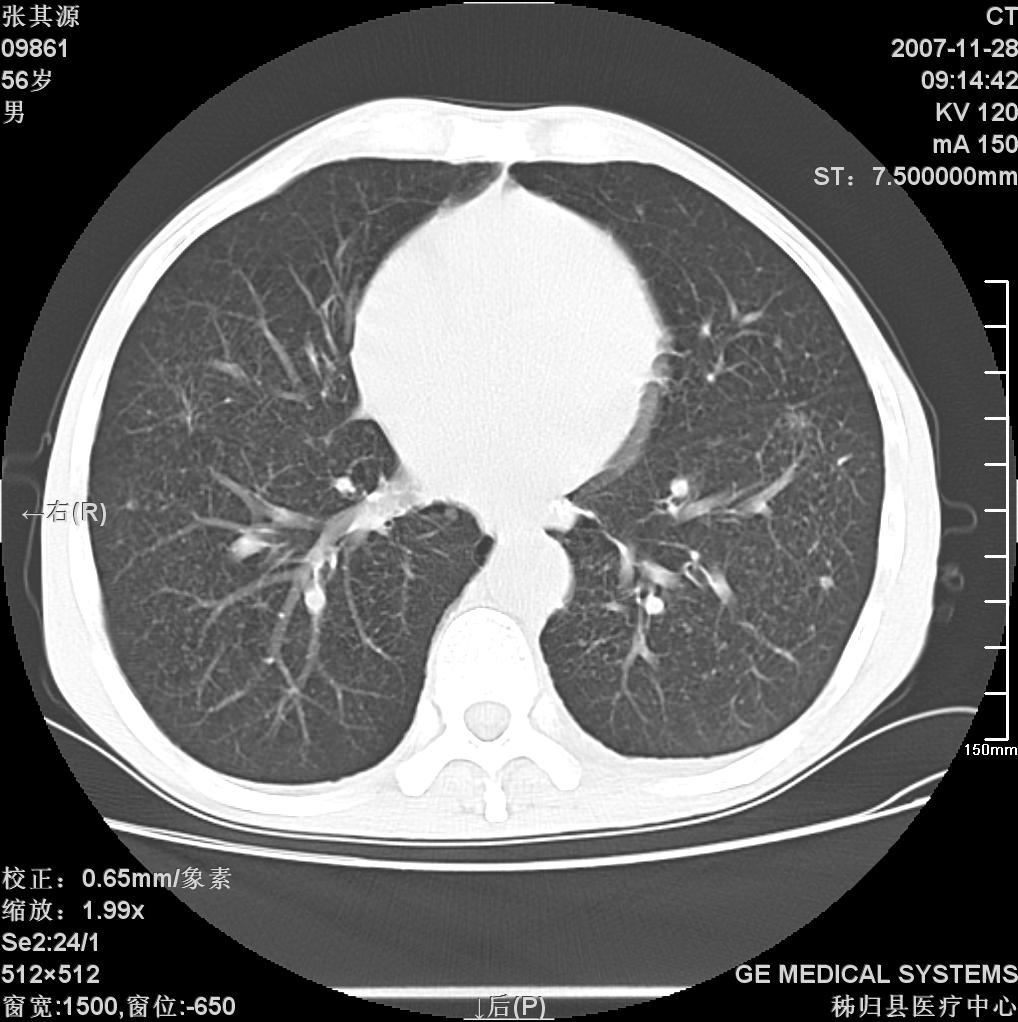

患者因阻塞性黄疸入院,发病前10天持续中等程度发烧.术前检查发现两肺弥漫性病变,请各位大虾会诊,除了考虑急性血源性肺结核外,还有其他什么疾病可能.

影像符合粟粒型肺tb改变。

两肺另见略大结节,结合病史,应考虑转移,有腹部片吗?肺内表现可有:结核?甲状腺癌肺转移?肺泡癌?

双肺多发粟粒样病灶,右肺胸膜下结节样病灶,气管前腔静脉后及隆突下均见肿大淋巴结,结合胆道肿瘤病史首先考虑转移。另外心影密度略低,时间格显示,是否有贫血?查明白再手术吧!

肺气肿、细支气管炎。